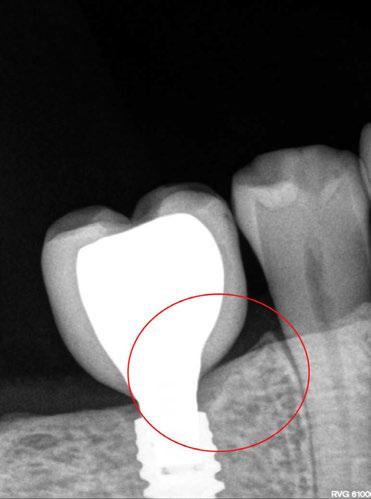

Para ilustrar el proceso, presentamos el caso de una mujer joven diagnosticada de carcinoma adenoide quístico en la región posterior del hemipaladar izquierdo (Figuras 1 y 2). El procedimiento quirúrgico realizado fue una

maxilectomía parcial que incluyó las piezas 24-26 y desde el reborde alveolar hasta la base del cráneo (Figuras 3 y 4). En este caso, la órbita y el globo ocular pudieron ser preservados. La reconstrucción inmediata se realizó mediante un colgajo de músculo temporal homolateral (Figura 5) y el defecto de la fosa temporal fue cubierto mediante una malla de titanio. Posteriormente, la paciente recibió radioterapia (Figuras 6 y 7). 2 años más tarde se diseñó un IS con anclaje en el arbotante nasomaxilar, zona subnasal izquierda

y lo que se pudo preservar del hueso malar. Se añadió una malla sinterizada infraorbitaria para dar volumen a la mejilla y se planificaron dos brazos de conexión que emergieran en las posiciones 24 y 26 de forma subgingival (Figuras 8 y 9). La superficie interna que apoyaba en el hueso era de titanio microrrugoso, y la superficie externa y conectores de titanio pulido y hexágono externo universal (Figuras 10 y 11). La cirugía se hizo bajo anestesia general en infiltración con anestesia local (4% articaína, 1:100.00 epinefrina), levantando el

colgajo cutáneo de la mejilla por vía intraoral, preservando el colgajo temporal para no comunicar con el remanente de la cavidad naso maxilar (Figura 12). Se emplearon 10 tornillos de osteosíntesis de 1,9 mm y la estabilidad primaria obtenida fue excelente (Figura 13)